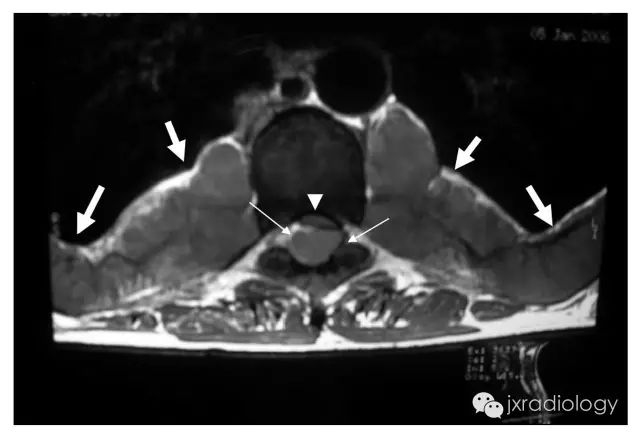

髓外造血器官,影像学上通常表现为器官增大,如超声、CT或MRI上表现为肝肿大、脾大。然而,在不常见的情况下,髓外造血可以发生在胸腔内,呈后纵隔肿块,变现为单侧或双侧脊柱旁肿块,边缘光滑,轮廓分明,常呈分叶状边缘。